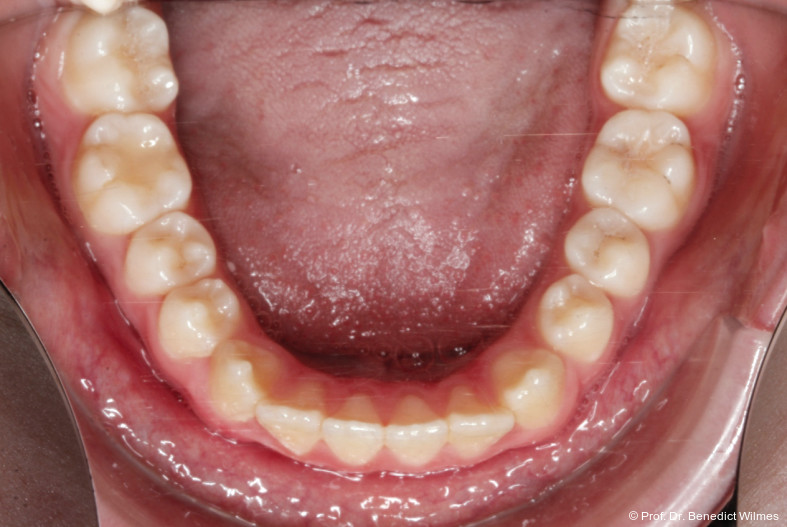

Eine 13-jährige Patientin stellte sich mit beidseitigem Kreuzbiss, einem anterioren offenen Biss und einer Angle Klasse II vor. Das viszerale Schluckmuster wurde mittels logopädischer Maßnahmen umgestellt, der offene Biss persistierte jedoch (Abb. 3a–l).

Nach erfolgreicher Expansion und Molaren­intrusion wurde eine Multibracket-Therapie zur Ausformung und Koordination der Zahnbögen durchgeführt (Abb. 8a–f). Nach Abschluss der aktiven Behandlungsphase wurden die Apparaturen entfernt und festsitzende Retainer im Ober- und Unterkiefer eingesetzt (Abb. 9a–k).